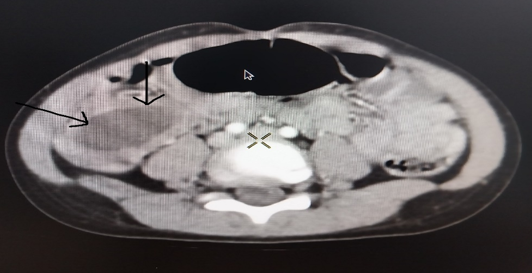

và thăm dò chức năng cần thiết: Qua hình ảnh chụp cắt lớp vi tính có thuốc cản

quang ổ bụng phát hiện hình ảnh “Nang ruột đôi” kích thước 39 x 27 mm .

Hình ảnh nang ruột đôi trên phim CT Scanner ổ bụng